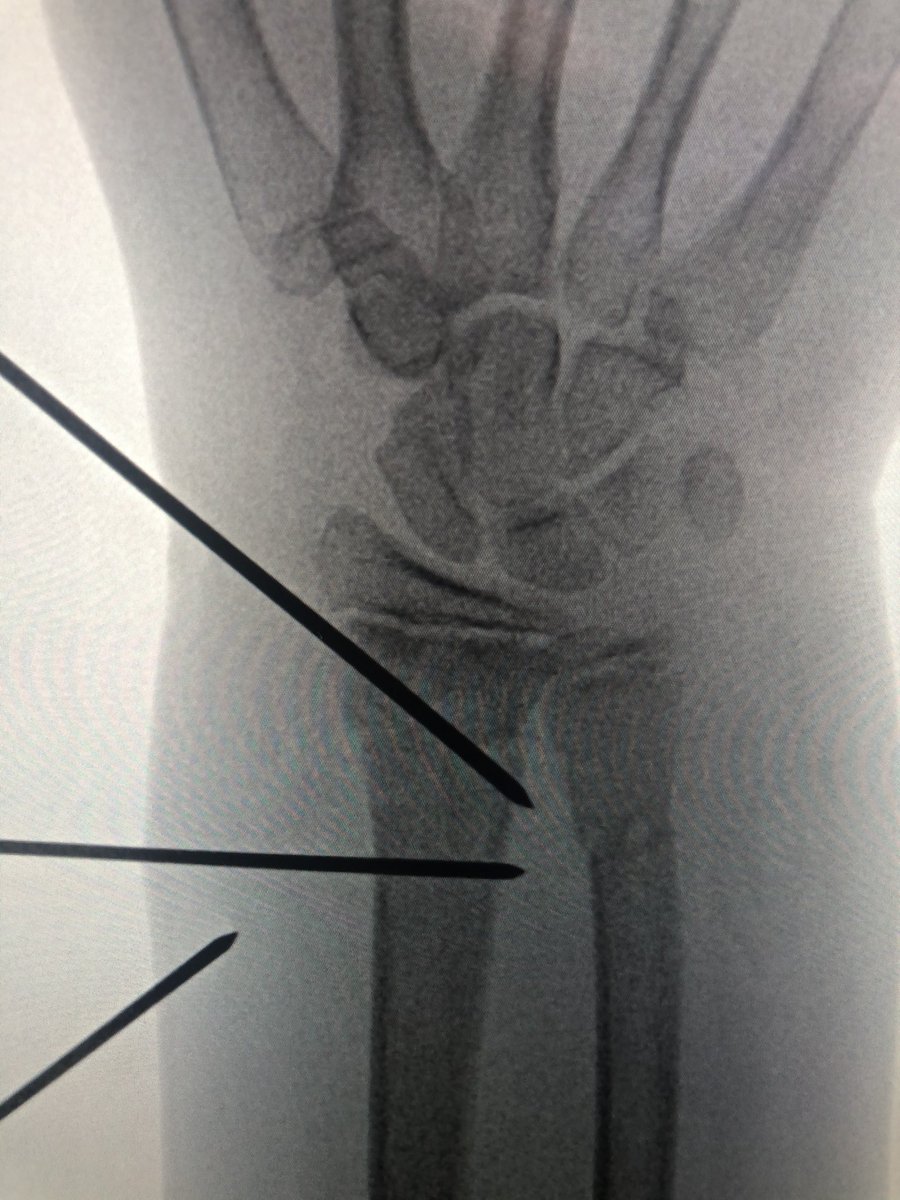

[2/4] This is the best closed reduction I could get and I didn’t want the morbidity of opening it to get it better. So I lined up the wire distal to the physis, and another one further proximally. The distal wire is smooth, but the proximal is threaded.... why?...